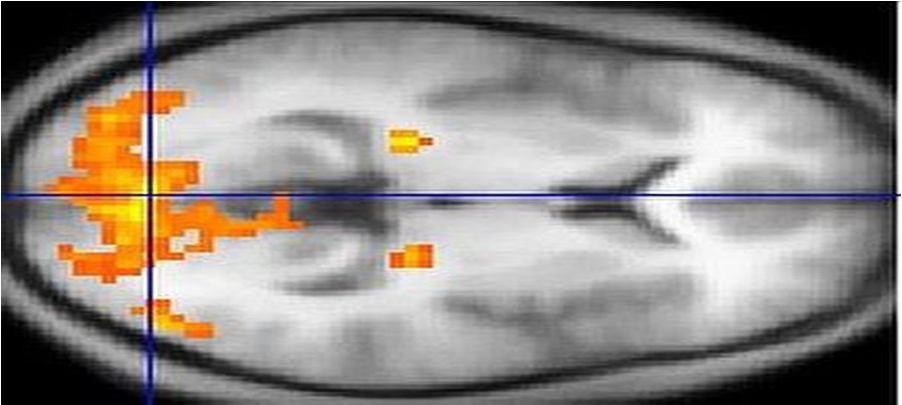

Figure 3: An MRI scan showing regions of activation in orange, including the primary visual cortex.